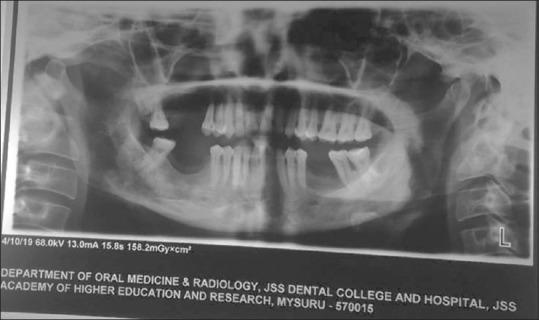

成人起病的朗格汉斯细胞组织细胞增多症——口腔中的“特洛伊木马”:一例罕见临床表现的病例报告

Adult-onset Langerhans cell histiocytosis - A Trojan horse of oral cavity: A case report with rare clinical presentation.

Department of Oral Medicine and Radiology, JSS Dental College and Hospital, JSS Academy of Higher Education and Research (JSSAHE&R), Mysuru, Karnataka, India.

Langerhans cell histiocytosis (LCH), earlier recognised as histiocytosis X, is a rare haematological illness involving infants and young children. LCH is caused by unrestrained stimulation and proliferation of usual antigen presenting cells, Langerhans cells (LCs) and the disease demonstrates extensive clinical and radiographic features involving multiple sites. Since the incidence is relatively low limited data is available regarding the epidemiology of LCH, with approximation of 2-5 cases per million populations per year. LCH has male predilection with jaws involved in 10-20% cases and only 1% of the cases affecting maxilla, masquerading as periodontal or periapical pathology. We report a case of 48-year-old female with LCH involving posterior maxilla. This is a unique presentation corresponding to age, gender, location and severity. Dental clinicians should be aware of this and consider it to be a part of their differential diagnosis pertaining to unresolved periodontal pathology as it mimics clinically and radiographically.

朗格汉斯细胞组织细胞增多症(LCH),早期被称为组织细胞增多症X,是一种罕见的血液疾病,主要累及婴幼儿。LCH是由通常的抗原呈递细胞——朗格汉斯细胞(LCs)不受控制的刺激和增殖引起的,该疾病表现出涉及多个部位的广泛临床和影像学特征。由于发病率相对较低,关于LCH流行病学的可用数据有限,每年每百万人口中约有2 - 5例。LCH男性多见,10% - 20%的病例累及颌骨,仅占上颌骨病例的1%,常表现为牙周或根尖周病变。我们报告一例48岁女性LCH累及上颌后部的病例。这是一个在年龄、性别、部位和严重程度方面都很独特的表现。牙科临床医生应意识到这一点,并将其视为与未解决的牙周病变相关的鉴别诊断的一部分,因为它在临床和影像学上都有相似表现。